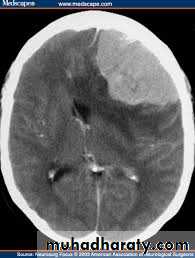

Brain Herniation

Supratentorial herniation

• Uncal (transtentorial)• Central

• Cingulate (subfalcine)

• Transcalvarial

Ocular:Hutchison's pupil -uncal herniation

Miotic sluggishly reacting to light – pontineMidsized or Mydriatic fixed to light – Midbrain